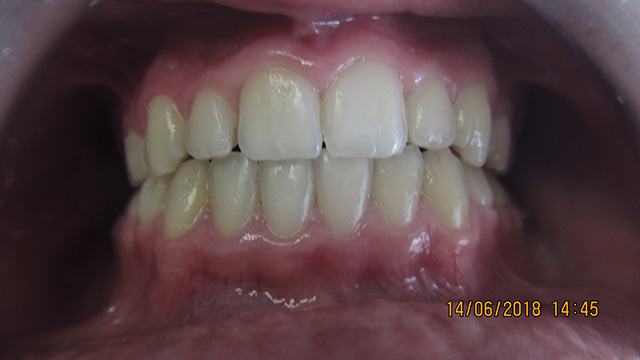

Lekua faltaren ortodontzia